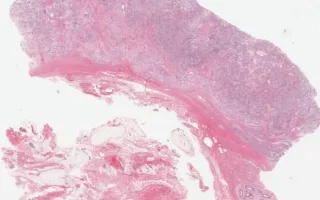

Testis (undescended), Yolk-sac tumour, H&E stain

Yolk sac tumours are the most common testicular tumours in infants and young children. They may also occur in adults, usually as a component of a mixed germ cell tumour. Microscopically, yolk sac tumours often have a heterogenous appearance with multiple architectural patterns. This case demonstrates a mixture of microcystic, reticular, glandular/tubular, and solid patterns amongst a variably myxoid stroma. Focal areas consistent with Schiller-Duval bodies are also seen (fibrovascular cores with tumour cells, surrounded by cystic spaces and a second layer of tumour cells, resembling glomeruli). Intercellular eosinophilic globules are also seen throughout the tumour and are composed of alpha-fetoprotein (AFP) and alpha-1-antitrypsin. AFP staining by immunohistochemistry is characteristic of this tumour (see accompanying slide with AFP immunohistochemistry).

Cryptorchidism is the most common birth defect of the male genital tract and is characterized by the failure of the testes to descend into the scrotal sac. Cryptorchidism, if left uncorrected, is associated with sterility and an increased risk of developing testicular cancer. Microscopically the changes of cryptorchidism can be seen within the seminiferous tubules which are often smaller than normal with thickened and hyalinized basement membrane and varying degrees of germinal hypoplasia.

This slide shows H&E stain. See Related Content section for AFP stain.